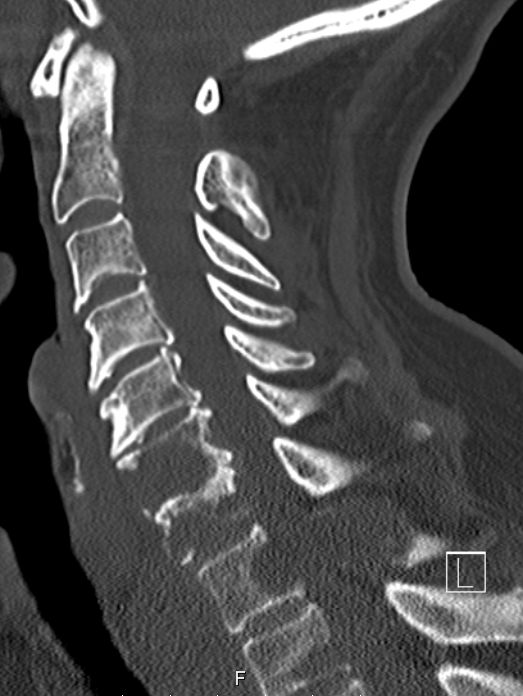

64-jähriger Mann mit einer Osteolyse C6/C7.![]() | |||